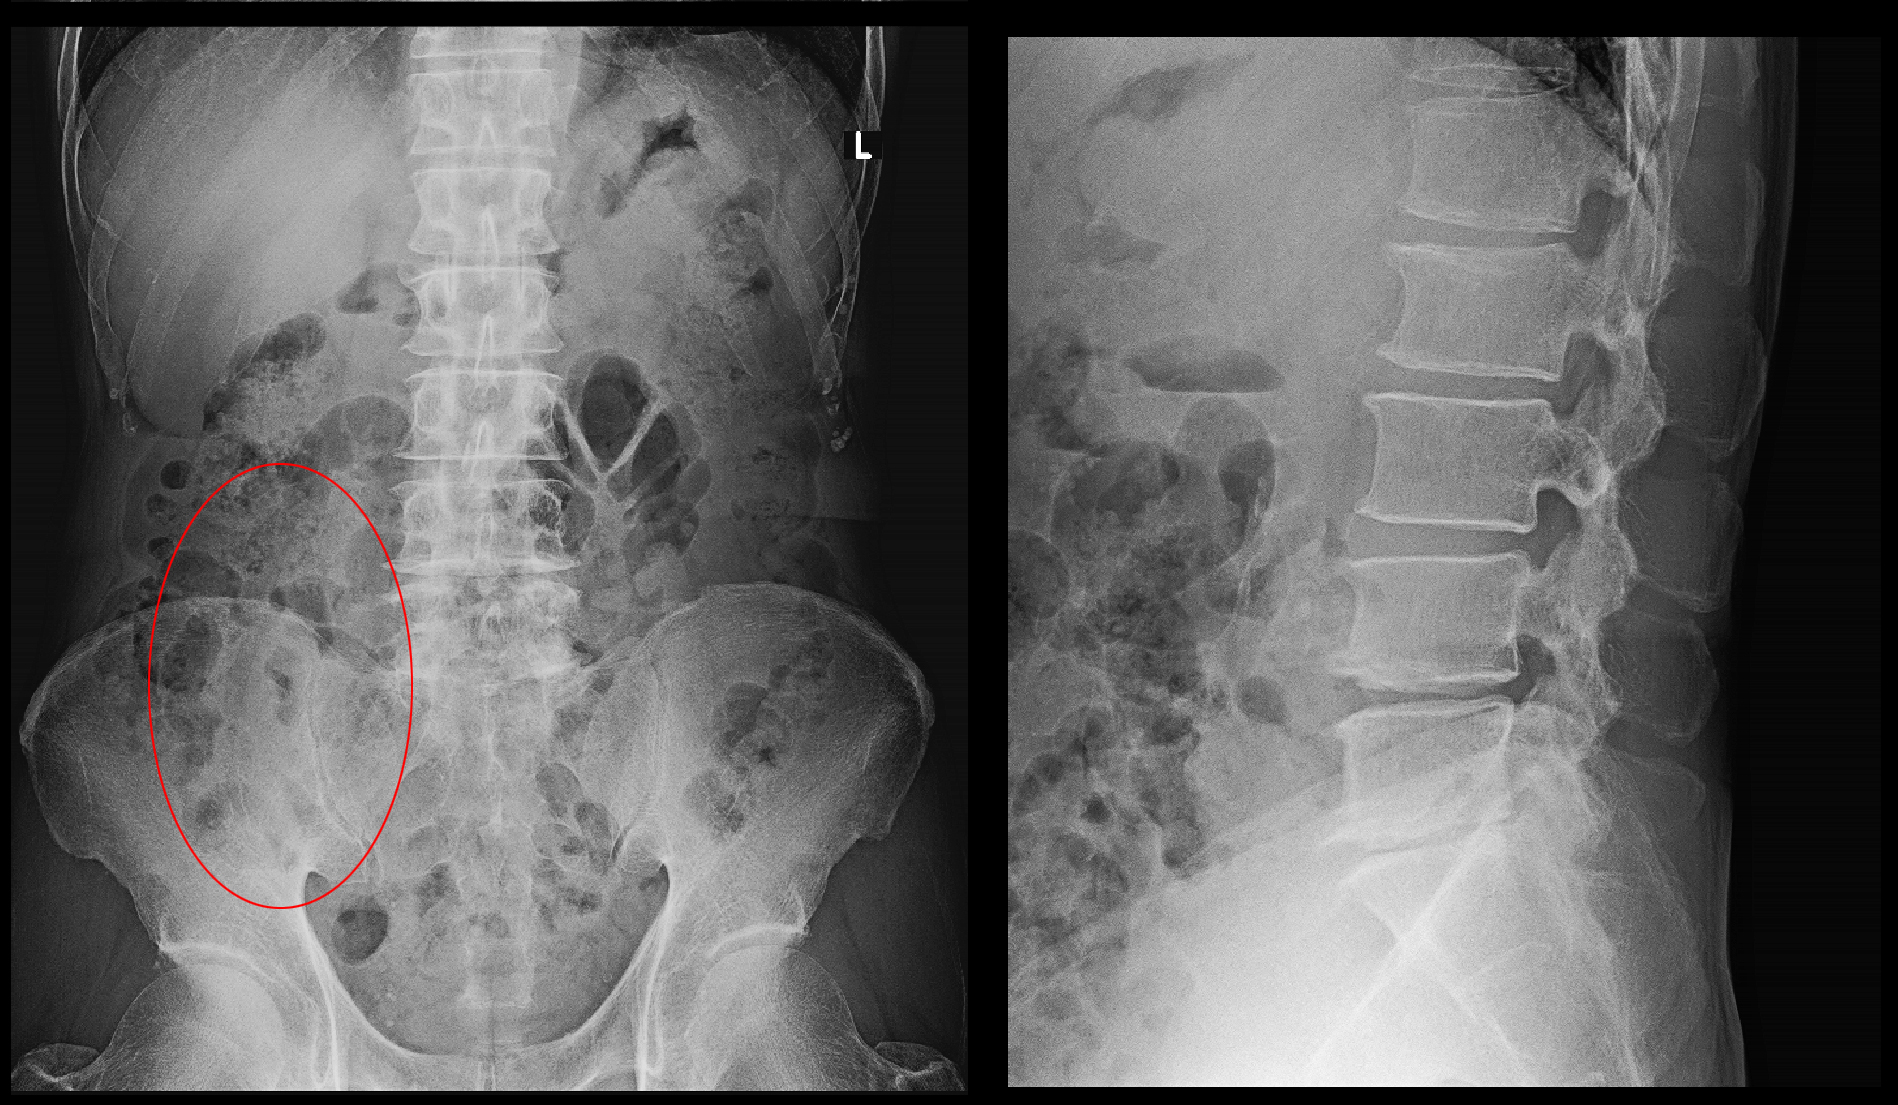

71才男 Xp.jpg

レントゲン像ではL4と5,L5と骨盤(S)の間の椎間板が狭くなっていて、老化を示す所見ですが、70才を過ぎていれば誰しもこの程度の老化の所見があって当然のものです。